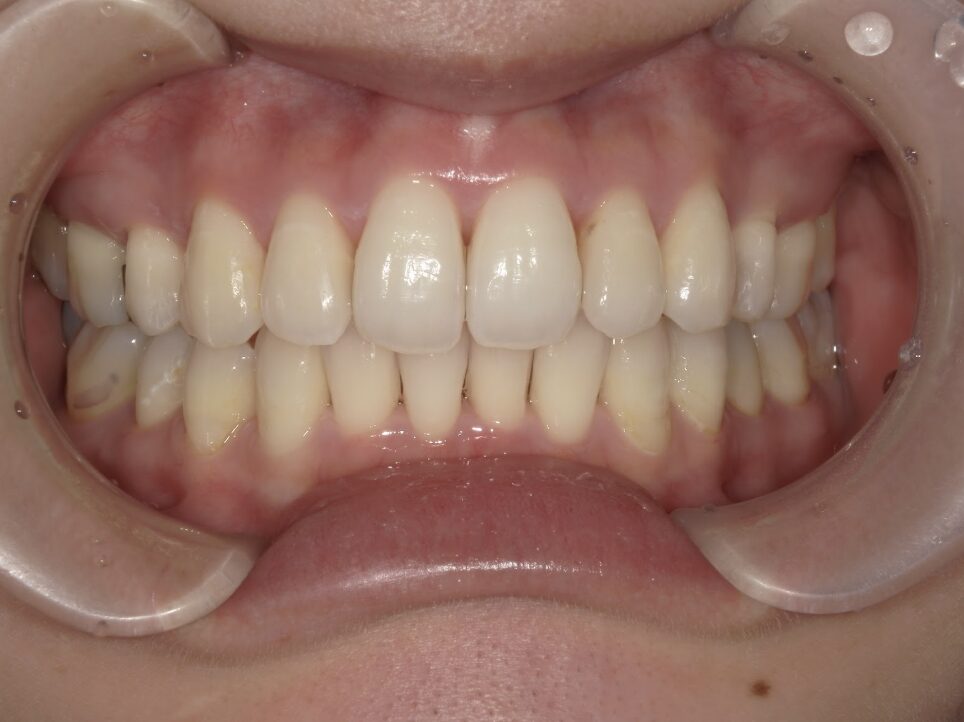

治療後

前歯が全く当たっていないを主訴に当院を受診され、開咬・上顎前突・下顎叢生を認めました。

上顎左右4番抜歯を行いIPRを使用してマウスピース型矯正装置(インビザライン)を使用し、改善を行いました。

治療期間1年9ヶ月